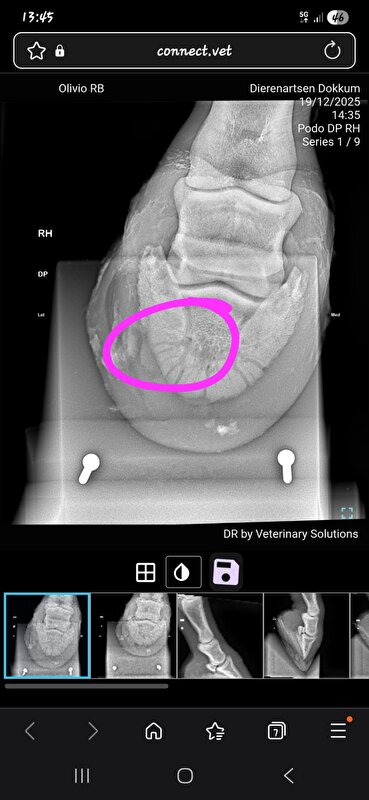

Mijn merrie is 1 januari 2025 kreupel uit de paddock gekomen. Wrs met een zooitje aan de ren geweest op de bevroren paddock, voet verkeerd neergezet of ergens tegenaan getrapt en ook hoefbeen gebroken. Echt gewoon domme pech geweest volgens de DA. Schijnt ook vaker voor te komen als de grond bevroren is.

Die van mij mocht na 6 maanden stalrust (wel echt op stal, en ook een rond ijzer) weer naar buiten. Ging toen ook over op een normaal ijzer. Zijn wel na zo'n 2,5e maand weer begonnen met stappen ad hand. Uiteindelijk heeft ze door een operatie aan mijn kant in totaal 8 maanden op "stal"rust gestaan (laatste 2 maanden in de opfok in een stal van 5x10m). Na 8 maanden de laatste foto's gemaakt, ijzer is er compleet onderuit gegaan, naar buiten toe opgebouwd (had dus al 2 maanden eerder gemogen maar ging niet op de stal waar ze toen stond) en sinds 1 november staat ze eindelijk weer op een normale pensionstal.

We hebben hier wel de 6 maanden volgemaakt en ik heb in het proces nog een keer een second opinion aangevraagd maar die gaven eigenlijk hetzelfde aan. Maar het zal wrs ook afhankelijk zijn van de grootte en de plek van de breuk en hoe vlot het hersteld.

Liep hier alleen helaas wel door tot het gewricht

Ben zelf dus vooral bang voor potentieel artrose op "jongere" leeftijd maar ook de second opinion was heel tevreden over de genezing dus hopelijk valt dat mee

DA heeft daar verder ook weinig over gezegd maar dat is echt iets wat de tijd uit zal moeten gaan wijzen. Dat die van jou dat niet heeft klinkt iig gunstig! Alhoewel ze bij jou miss wat sneller bang zijn dat dat hoekje kan gaan "verschuiven"?